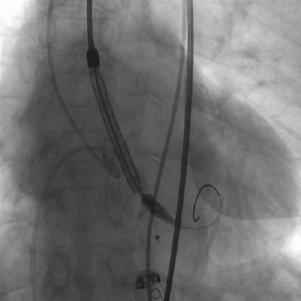

患者麻醉方式采取全麻,建立静脉通路后,穿刺左侧股动脉,建立副入路。在超声引导下精准穿刺右股动脉及股静脉,预埋两把ProGlide缝合器,置入20F动脉鞘管,漂浮电极经股静脉送至右室心尖。跨瓣成功后,将Lunderquist导丝送入左心室, 23mm球囊预扩张,Venus-A 29瓣膜精准定位并释放,术中造影及超声反馈良好,瓣膜形态良好,结果满意。

输送器定位

瓣中瓣释放